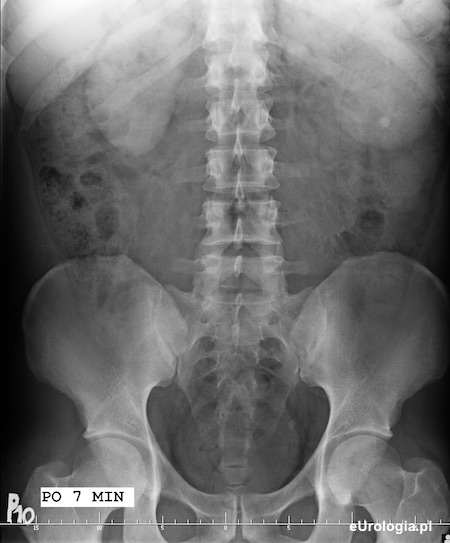

Zdjęcie urograficzne wykonane w 7 minucie po dożylnym podaniu kontrastu - widoczny nefrogram obu nerek